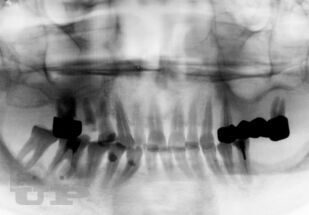

В учебном пособии на современном исследовательском уровне обобщены и подробно изложенылечение и профилактика заболеваний пародонта. Схемы этиопатогенетического лечения заболеваний пародонта постоянно совершенствуются и с успехом используются на протяжении многих лет на кафедре терапевтической стоматологии и в поликлиниках города. Авторы надеются, что издание поможет врачам-стоматологам, а также врачам других специальностей в назначении комплексного, индивидуализированного, этиопатогенетического лечения заболеваний пародонта.